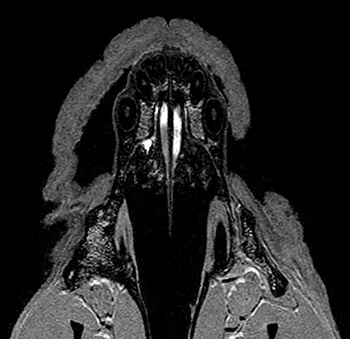

1. L'organe voméronasal (VNO) est constitué d'une paire de sacs tubulaires borgnes, enfermé dans une capsule cartilagineuse, dans le plancher des cavités nasales, le long de la base du septum nasal (MRI Features of the Vomeronasal Organ in Dogs (Canis Familiaris) 2020).

(Photo : vetopsy.fr d'après Dzięcioł et coll)